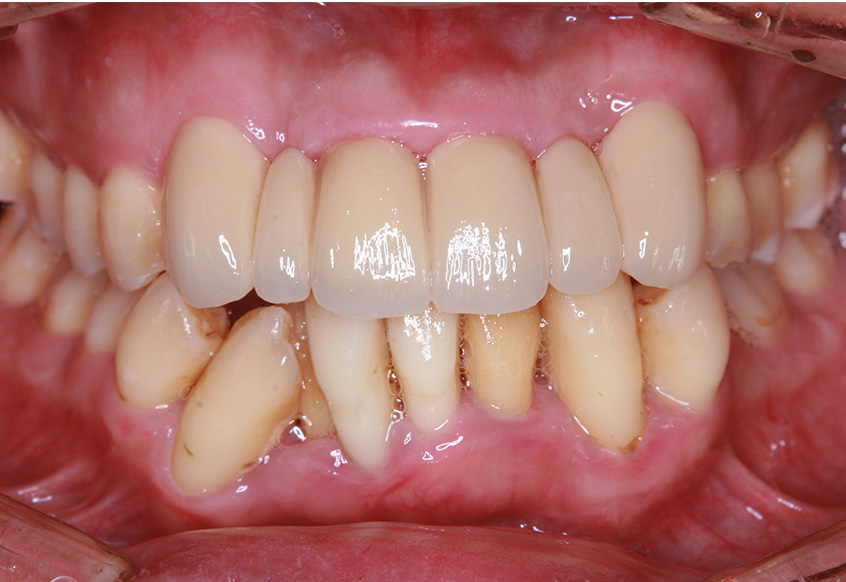

最初のお口の中 ワイヤー装着して治療を開始

-

治療開始後3ヵ月経過すると、前歯の隙間や全体の乱れが減ってきました。口笛が吹けるようになったとのことです。

最初のお口の中 治療開始3ヵ月後

6ヵ月経過すると、矯正治療を終了し、前歯に被せ物の治療を行いました。

最初のお口の中 2025/3/22

被せ物装着

当院では、歯並びが気になる人に対して、矯正治療を行っています。また今回の症例のようにワイヤーを用いた治療からマウスピース矯正治療も行っておりますので、スタッフにお声かけください。

| 患者属性 | 30代男性、歯科恐怖症 |

|---|---|

| 主訴 | 上の前歯の歯並びを整えたい |

| 診断 | 歯列不正、う蝕歯 |

| 矯正装置 | 矯正ブラケットとワイヤー |

| 治療期間 | 約6ヵ月 |

| 通院回数 | 8回 |

| 治療費 | 矯正:基本料金(220,000円)+調整料(5,500円×6回)、補綴治療:72,600円、費用は税込 |

| 治療内容 | 上顎側切歯を2本抜歯した後、上顎の歯にブラケットを装着し、ワイヤー、矯正用ゴムで歯の移動を行いました。その後、被せ物の治療を行って治療を終了しています。 |